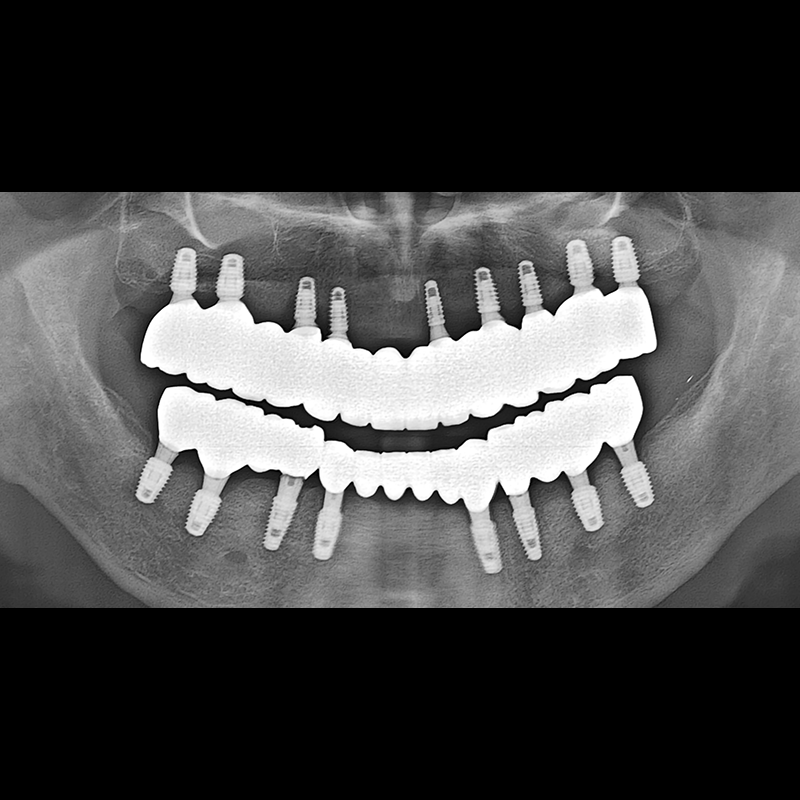

BEFORE AFTER

种植牙前后的照片 2025.05.30

在缺失的牙齿部分和难以挽救的牙齿位置植入了种植牙。